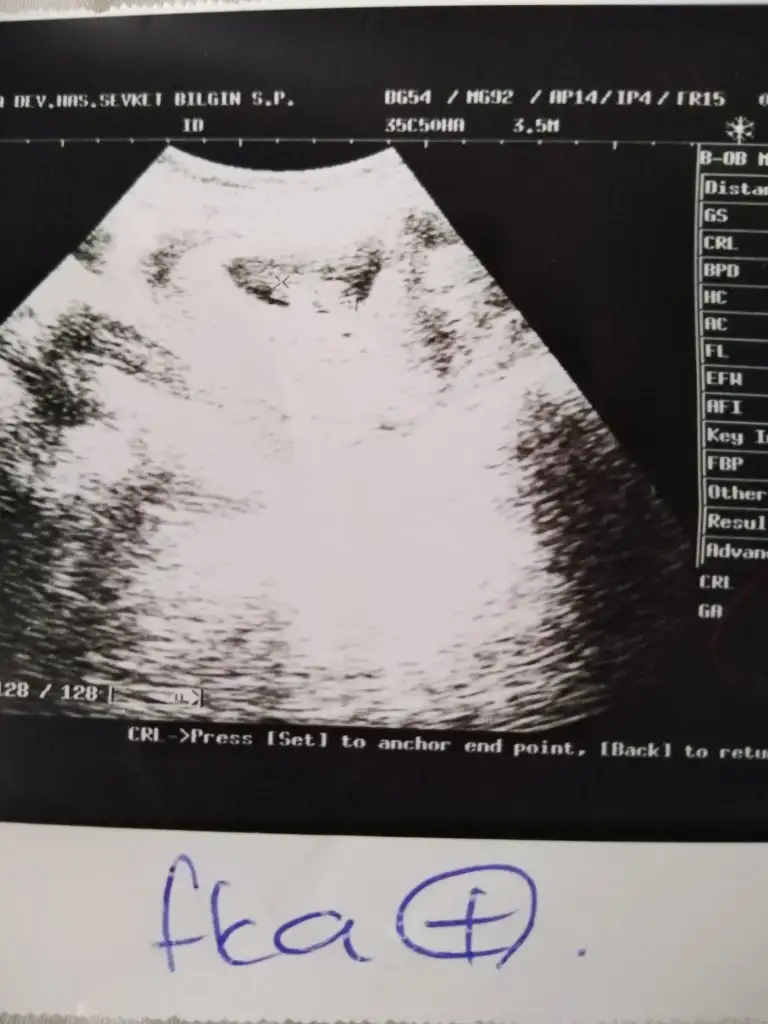

Selamlar herkese 5+5 haftalık bebişim. vajinal bakıldı.sizce kızmı erkek mi